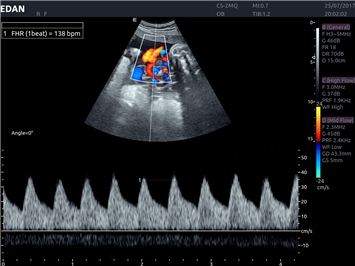

EDAN Acclarix LX4

Расширьте свои представления. Использование усовершенствованной платформой Acclarix система LX4 обеспечивает непревзойденную четкость изображений и интеллектуальный рабочий процесс для всех пользователей, являясь при этом наиболее экономичным решением.

EDAN Acclarix LX4 представляет собой инновационную ультразвуковую систему, построенную на усовершенствованной платформе Acclarix. Сочетание высокого качества визуализации с интеллектуальным рабочим процессом делает эту систему оптимальным выбором для клиник, ценящих эффективность и экономичность.

Цветовой допплер:

Да

Импульсно-волновой допплер: